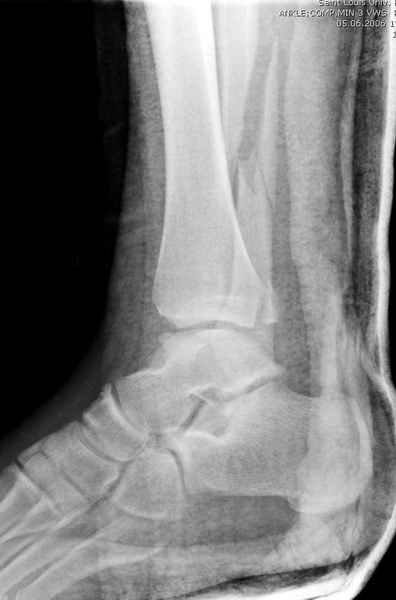

>На сделанных у нас снимках видно, что не все благополучно...

Неравномерность суставной щели может быть связана с разрывом глубокой порции дельтовидной связки и ротацией м/берцовой кости за счет поврежденных структур синдесмоза(репозиция ее на уровне перелома как-будто удовлетворительная).

По моему мнению,ассиметрия суставной щели обусловлена импрессией медиальной части суставной поверхности б/б кости. Да, позиционный винт здесь не лишен, но через 4 недели целесообразность его проведения сомнительна, брейс, ограничение осевой нагрузки достаточно.Есть еще деонтологические аспекты повторной операции, не все так плохо выполнено предыдущим доктором!

Клиновидность щели сустава следствие повреждения дельты, невосстановления длины малоберцовой или (хотел сказать "установки в гипсе", но оного, вроде,

нет)? Устранить бы причину. А равно как и тенденцию" к наружному подвывиху. Чрескостный остеосинтез - метод выбора.

Мое мнение, что никакой ротации малоберцовой кости здесь нет и синдесмоз тоже впорядке. Все дело в некачественно репозиции медиального мыщелка. Скорее всего его или немного ротировали при операции или сместили латерально. Более склонен ко второму варианту.

Конечно, компьютерный томограф более информативный метод, но с помощью недорогого обычного стандартного в нейтральном положении стопы: прямого, бокового и косой (ankle mortise) ренгенологического метода можно получить полную информацию о повреждении голеностопного сустава, а сравнительный снимок с другой стороны подтвердить наличие повреждения.

При реконструкции голеностопа, о важности восстановления длины малоберцовой для профилактики пост травматического артроза разбирали в предыдущих дискуссиях. Нарушенную биомеханику голеностопа без восстановления длины малоберцовой, не восстановить только швом медиальной связки.

Расширенная медиальная щель более чем на 4 мм и укорочение малоберцовой более чем 2 мм, а перелом заднего края большеберцовой смещения более 2мм с вовлечением 30% поверхности сустава, считается отходом от нормы голеностопного сустава, и подлежит к оперативному вмещательству.